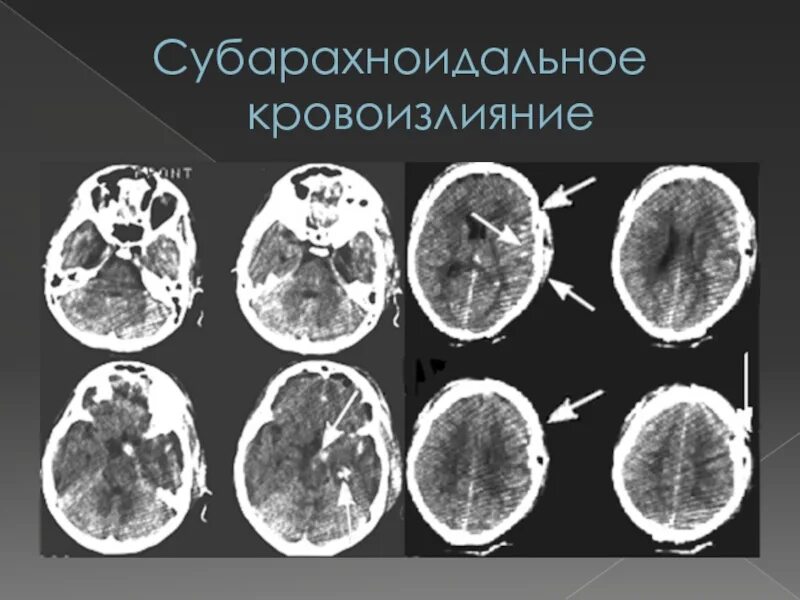

Кровоизлияние в мозг у новорожденного степени